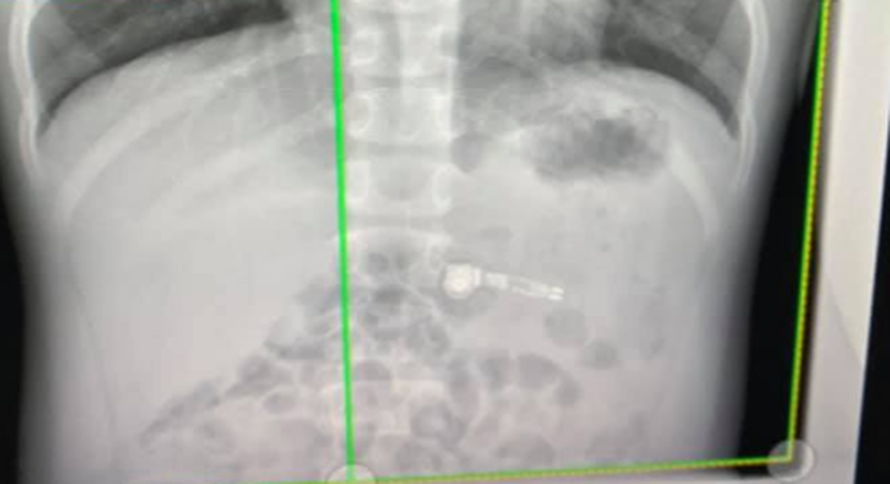

Roditelji, pripazite na djecu! Po novome, jedu AirPod slušalice

Mama je ispričala da se OJ-u slušalica prema grlu zaletjela jer je njezin duži kraj držao u ustima, a AirPod slušalice, koje je baš bio dobio za Božić, bile su u to vrijeme uparene s njegovim telefonom